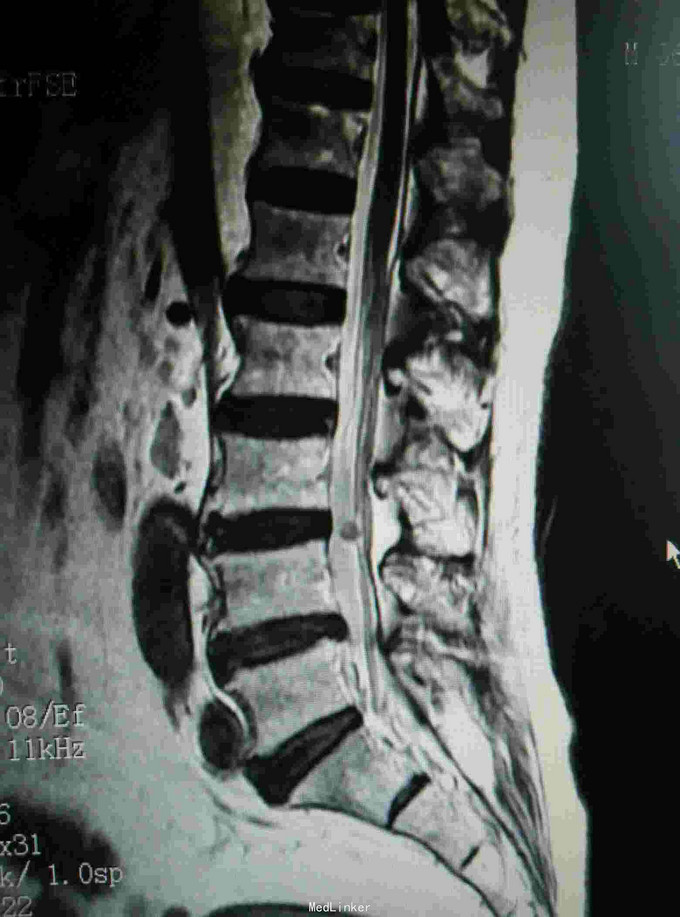

腰痛伴左下肢疼痛不适半月 患者无明显诱因出现腰痛,伴有沿左大腿根部后侧至外踝的疼痛,行走加重,休息可有缓解,期间未做特殊处理,外院核磁提示椎管内肿物,为求进一步诊治入我院。

查体:脊柱生理弯曲存在,腰骶部棘突及椎旁压痛,双下肢肌力IV级,双上肢肌力正常,下肢自主活动无异常,直腿抬高实验阴性,余检查无明显异常。 辅查:核磁提示L3-4椎管内肿物,L4-5椎间盘突出

诊断:椎管内良性肿瘤,腰椎间盘突出 治疗:椎管内肿物切除+腰椎内固定